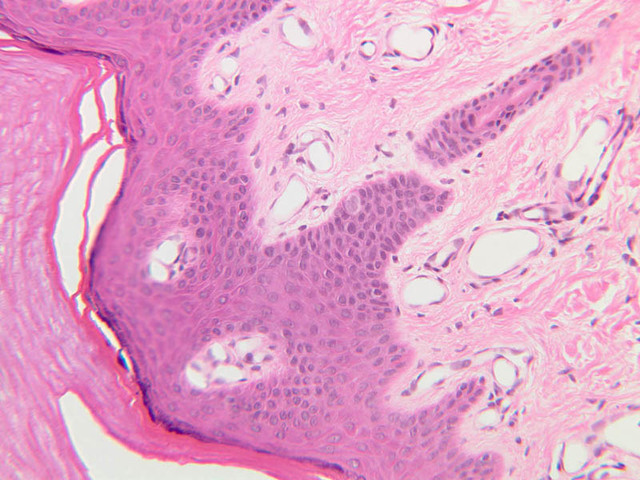

Examine slide A-50 (fingertip, H&E [2.5x, 10x-labeled, 20x, 40x-labeled] [20x, 40x] [10x, 20x, 40x] [20x, 20x, 40x]), and study the morphology of five layers of thick skin. The deepest part of the epidermis comprises the stratum basale which provides the cells required for continual renewal of the epidermis. This stratum is composed of a single layer of columnar or cuboidal epithelial cells attached to the basement membrane.

Superficial to the stratum basale is a multi-cellular layer known as the stratum spinosum, consisting of polyhedral cells that have a "prickly" or spiny appearance (A-50, langerhans cells [10x, 20x-labeled, 40x-labeled] [40x, 40x-labeled, 40x, 40x-labeled]; A- 48, abdominal skin, H&E [10x, 20x, 40x] [40x, 40x, 40x, 40x]). The spiny cells are separated by intercellular spaces that are bridged at numerous points by cytoplasmic processes, which in turn are bound together by desmosomes. The cytoplasmic processes projecting on all sides from the cells give them the spiny appearance to which the name refers. These are best seen under high power. Langerhans cells can also be found in this layer.

Superficial to the stratum spinosum is a layer of flattened cells with coarse, deeply-stained cytoplasmic granules, the stratum granulosum (slide A-50 [40x] [40x, 40x] [40x-labeled, 40x, 40x]). These are keratohyalin granules and evidently represent a stage in the keratinization of the epidermal cells. Note that the nuclei of the more superficial granular cells appear dense and pyknotic, foreshadowing their disintegration and the resultant death of the cells.

The stratum lucidum is often considered to be a subdivision of the stratum corneum. This layer is evident only in thick (glaborous) skin. It appears as a clear band beneath the stratum corneum. Cells of the stratum lucidum are well advanced in the process of keratinization. Consequently, the nucleus and many of the cytoplasmic organelles become disrupted and disappear as the cells become filled with the intracellular protein keratin. In many specimens, there is a separation artifact at this point. The outermost layer of the epidermis is called the stratum corneum and is composed of fully cornified (keratinized) remnants of epithelial cells ([40x]). It has a basketweave appearance. The close union of the resulting scales with each other, and their content of insoluble protein and extracellular lipids, provides a barrier to diffusion between the body and its external environment.